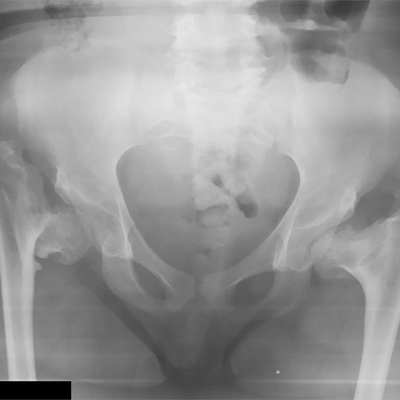

Click on an image below to view more info.